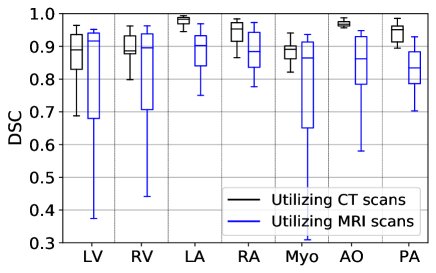

Fig. 7 exhibits the Box and Whisker visualization of all the methods showing the spreads and centers of the DSC, VOE, and Sn metrics for all the 20 test images, either CT or MRI scans.

The WHS results of the probabilistic atlas are exhibited in Table III, Fig. 7, and Fig. 8, where we employ our three methods, such as PAS, EM, and PAS+EM (see details in subsection II-B2). The PAS, EM, and PAS+EM schemes of probabilistic atlas provide the heart segmentation results with the mVOEs of , , and , respectively, for CT scans and , , and , respectively, for MRI scans. Table III exhibit that the PAS scheme exceeds the other two methods, such as EM and PAS+EM, by the margins of and for CT scans concerning the mDSC, respectively, whereas it also beats them by the margins of and for MRI scans, respectively, in terms of the mDSC. Similarly, the EM and EM+PAS are also defeated by the proposed PAS method for mVOE and mSn for both the chest imaging modalities with considerable margins (see in Table III). The spreads and centers of the DSC, VOE, and Sn metrics for all the 20 test images (either CT or MRI scans), as exhibited in Fig. 7, also reveal the supremacy of the proposed PAS method over the other two methods (EM and EM+PAS).

Fig. 9 reflects the Box and Whisker presentation of the mDSC of our proposed PAS algorithm on both the CT and MRI modalities for seven different substructures of the heart (see subsection I-A). The CT scans produce the best WHS results than the MRI scans for all the substructures in terms of mean and median values of the mDSC. The substructure’s segmentation results utilizing the MRI images also have a higher interquartile range than the CT images (see in Fig. 9), which indicates less robustness of the MRI images for the WHS. WHS’s poor results utilizing the MRI images over CT images are also reported in previously published articles [30, 5, 38, 1]. The segmentation results, especially for LA, RA, Myo, AO, and PA, utilizing the CT images, are praiseworthy as they have a high median value and significantly less interquartile range than MRI images.